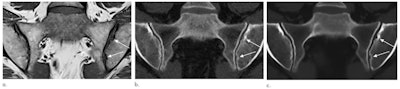

Images in a 51-year-old woman with erosions. (A) T1-weighted MRI, (B) CT, and (C) synthetic CT scans. Erosions (arrows) are clearly depicted on C but less clear on A. Images and caption courtesy of the RSNA.